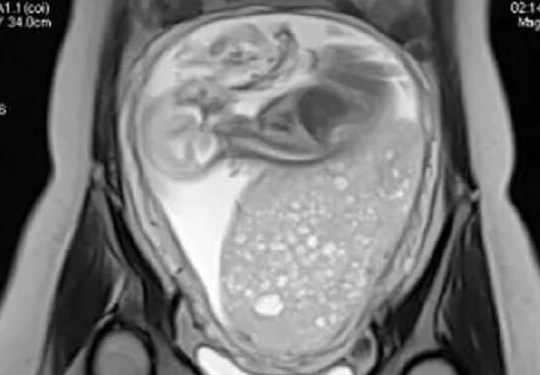

B超能够清晰地显示卵巢内卵泡的数量、大小和形态。医生通过定期的B超监测,可以实时了解卵泡的发育动态。比如,观察卵泡是否按照预期的速度生长,是否存在发育过快或过慢的情况。如果卵泡发育过快,可能意味着药物剂量过大,有卵巢过度刺激综合征的风险;若卵泡发育过慢,则可能提示药物剂量不足,需要调整用药方案。

此外,B超还能帮助医生判断卵泡的成熟度。成熟的卵泡通常具有一定的直径大小和形态特征,医生可以根据B超结果,准确把握取卵的最佳时机。如果过早取卵,卵子可能尚未成熟,无法完成受精;而过晚取卵,卵子可能已经老化,影响胚胎质量。